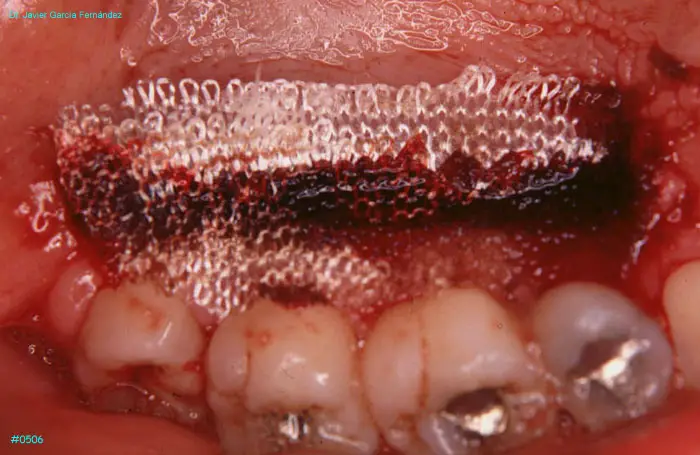

Atlas of Surgical Techniques in Periodontics. Chapter II. Atlas de Técnicas Quirúrgicas en Periodoncia